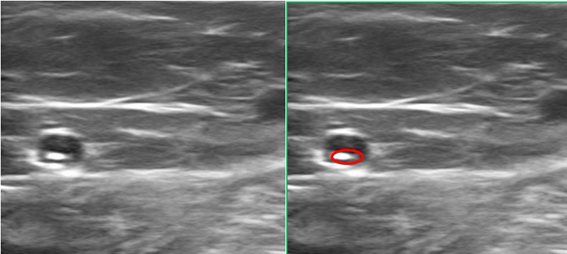

Figure 5A Cross-sectional ultrasound image. Intra-fascial Greater Saphenous Vein, showing Arrow catheter tip.

Administration is carried out under DUS, with slow administration of 2 cc of foam, and administration of another 2 cm of foam in withdrawal, observing the adequate distribution of the medication along the vein. Administration of the drug should be painless. In our case, Trendelenburg placement is performed prior to the administration of the foam, which increases the safety of the treatment while reducing the diameter of the vessel, facilitating contact with the endothelium of the Polidocanol foam, and improving its effectiveness.